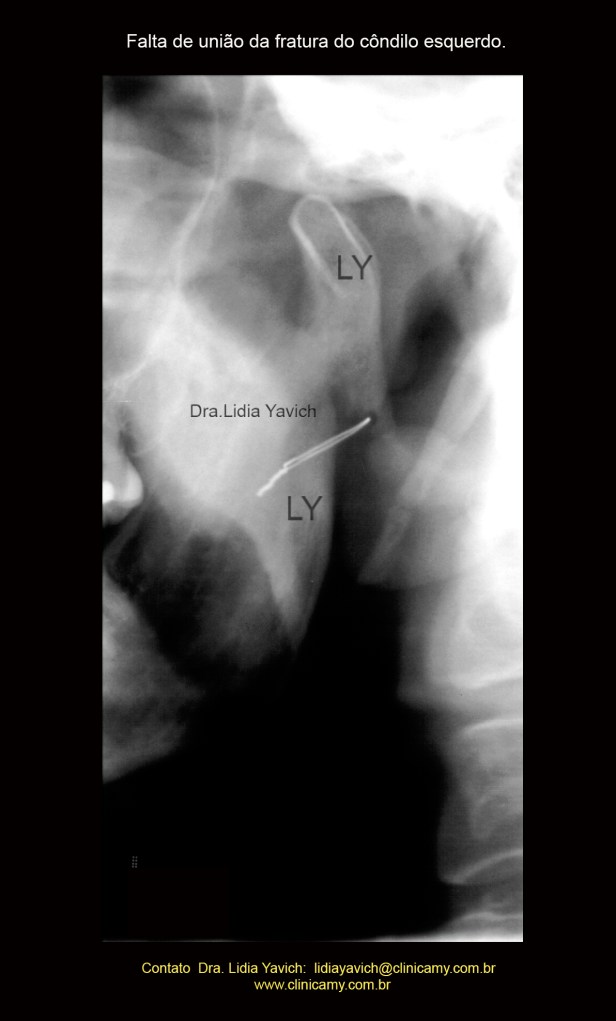

Laminografia das ATMs do paciente no dia da consulta evidenciando a falta de união da fratura do côndilo mandibular esquerdo.

Ampliação do côndilo mandibular esquerdo na radiografia panorâmica.